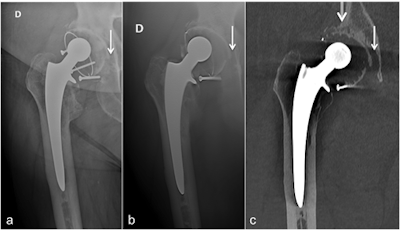

In the current study, 49 patients (23 women and 26 men) with painful hip prosthesis underwent x-ray, digital tomosynthesis, and CT-metal artifact reduction for prosthetic loosening between January 2012 and January 2016. The group deemed periprosthetic radiolucent lines wider than 2 mm in two or more Gruen or De Lee and Charnley zones as diagnostic of prosthetic loosening, and all prosthetic loosening cases were confirmed surgically. There were 21 cases of prosthetic loosening, nine of the acetabular component only, and 12 of both acetabular and femoral components (European Radiology, 7 September 2018).

The radiologists evaluated the images in four readout sessions (conventional x-ray only, digital tomosynthesis only, CT-metal artifact reduction only, and x-ray associated with digital tomosynthesis) with at least a two-week interval between them. They based analysis on the evaluation of each zone of Gruen and De Lee and Charnley for the presence or absence of periprosthetic radiolucency.

The authors noted for both the acetabular and femoral sides, digital tomosynthesis had a specificity for prosthetic loosening detection similar to that of x-ray and CT-metal artifact reduction and a sensitivity similar to x-ray but lower than CT-metal artifact reduction. The results are shown in the table below.